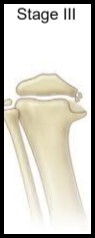

16

Q

Doença de Blount

Langenskiöld III ?

A

4 - 6 anos

* Início da deformidade na fise para formação da ponte óssea

17

Langenskiöld IV ?

5 - 10 anos

* Formação da barra óssea

É DE 4 QUE A BARRA ENTRA

18

Langenskiöld IV - Marco em Relação ao TTO ?

Limite para OSTEOTOMIA